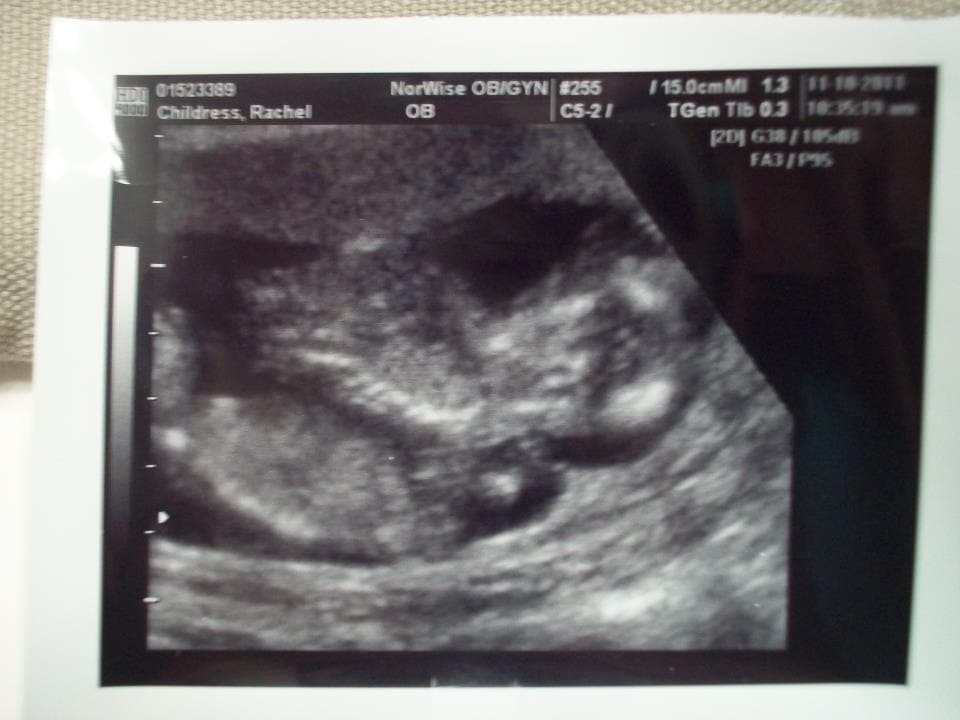

Ultrasound Photos at 15 Weeks Pregnant With Twins